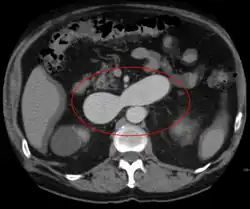

In the circulatory system, arteries carry blood away from the heart to the lungs and the rest of the body, where the blood normally passes through capillaries—where oxygen is released and waste products like carbon dioxide (CO2) absorbed—before veins return blood to the heart.[9] An AVM interferes with this process by forming a direct connection of the arteries and veins, bypassing the capillary bed.[10] AVMs can cause intense pain and lead to serious medical problems. Although AVMs are often associated with the brain and spinal cord, they can develop in other parts of the body.[10]

As an AVM lacks the dampening effect of capillaries on the blood flow, the AVM can get progressively larger over time as the amount of blood flowing through it increases, forcing the heart to work harder to keep up with the extra blood flow. It also causes the surrounding area to be deprived of the functions of the capillaries. The resulting tangle of blood vessels, often called a nidus (Latin for 'nest'), has no capillaries. It can be extremely fragile and prone to bleeding because of the abnormally direct connections between high-pressure arteries and low-pressure veins.[11] One indicator is a pulsing 'whoosh' sound caused by rapid blood flow through arteries and veins, which has been given the term bruit (French for 'noise'). If the AVM is severe, this may produce an audible symptom which can interfere with hearing and sleep as well as cause psychological distress.[1]